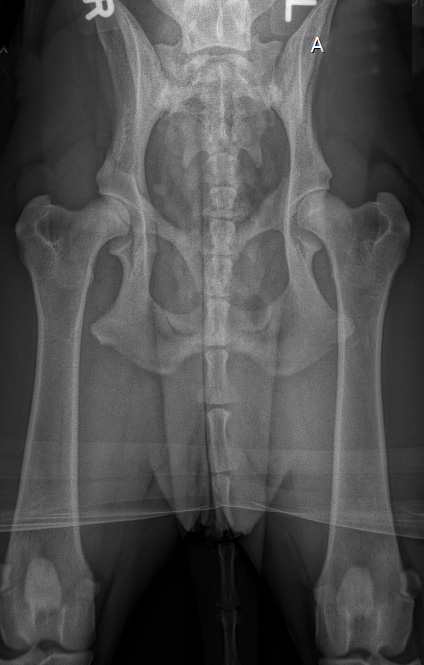

![]() HD-D/ HD-mittel/ HD 3 |

D |

= Grad2 (mittelgradig) |

HD-3 |

mittel |

Gravierende Veränderungen mit arthrotischen Zubildungen, NORBERG-Winkel zwischen 90 und 100 Grad |